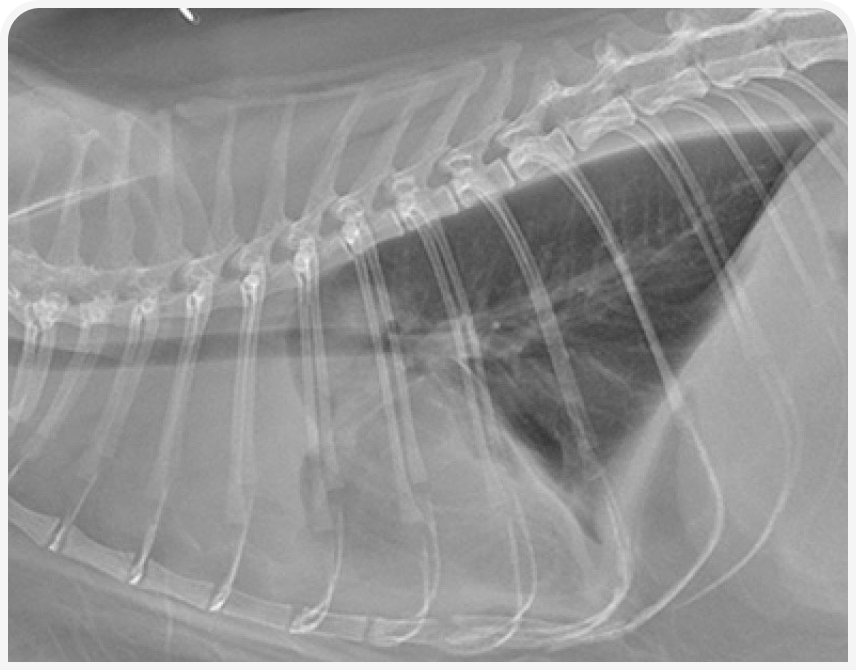

При рентгенографии органов грудной клетки можно выявить четко визуализируемое объемное образование в средостении (Рисунок 1), хотя иногда значительный плевральный выпот может затруднить визуализацию или сделать ее невозможной до тех пор, пока его не дренируют (Рисунок 2), поэтому могут потребоваться повторная рентгенография или УЗИ (Рисунок 3).